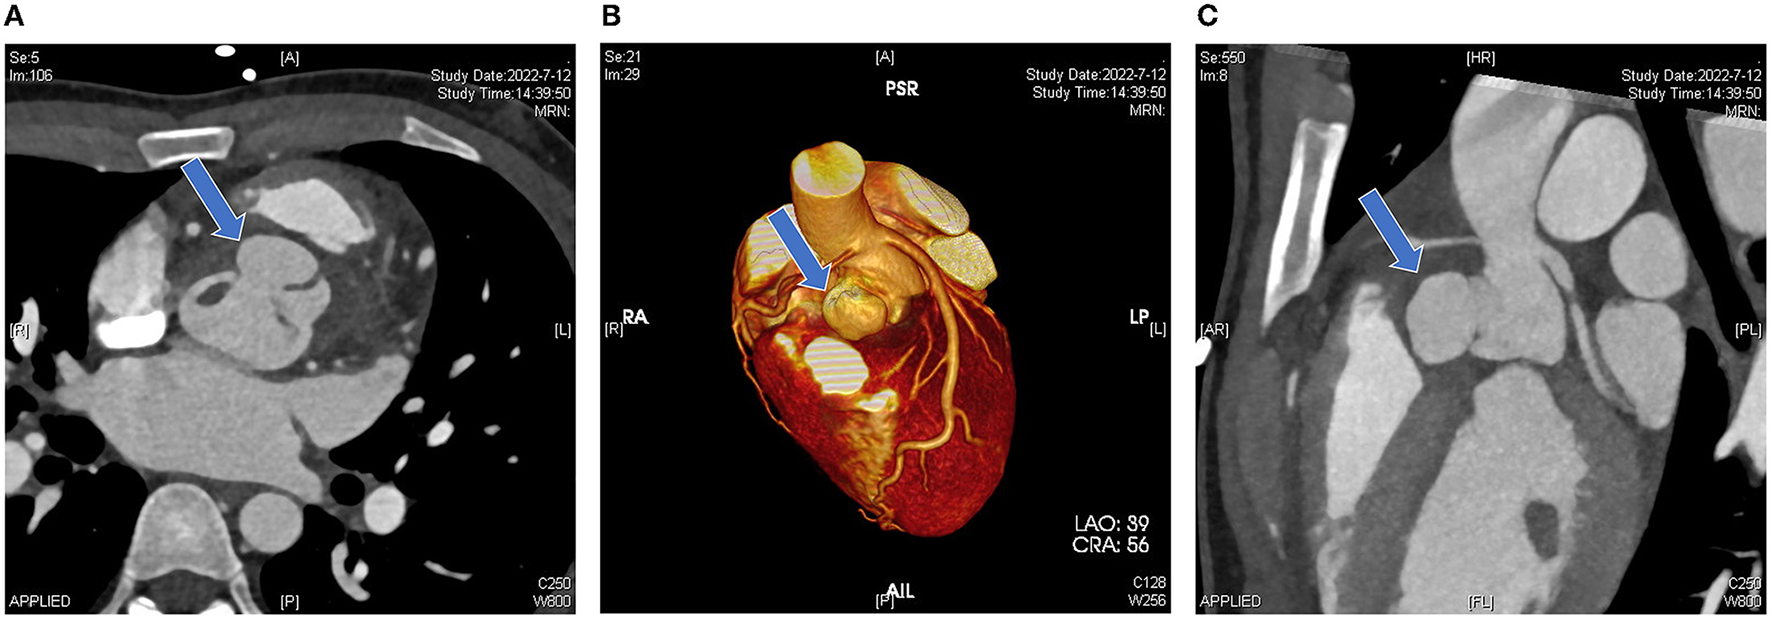

Computed tomographic angiography showed that the right coronary sinus was of an irregular shape, and was pushed to the left by a 2.2 × 1.4 × 2.1 cm cystic structure in the anterior part of the aortic root. Enhancement was observed in the cystic structure, which communicated with the aorta (Figure 2A); the left coronary artery arose from above the left coronary sinus; the right coronary artery arose from above the junction of the left and right coronary sinus, and the proximal segment was surrounded by the abscess (5.1 × 2.0 cm), resulting in mild-to-moderate stenosis (Figures 2B, C). Coronary angiography was not performed. Cranial MRI indicated no intracranial infection.

Figure 2

Pre-operative computed tomography. (A) Irregular morphology of the coronary sinuses with local anterior protrusion (blue arrow). (B) A three-dimensional reconstruction image shows that the left coronary artery arises from above the left coronary sinus and the right coronary artery arises from above the junction of the left and right coronary sinuses. The aortic root bulge is shown in the blue arrow. (C) Sagittal view showing the vertical position of the bulge (blue arrow).